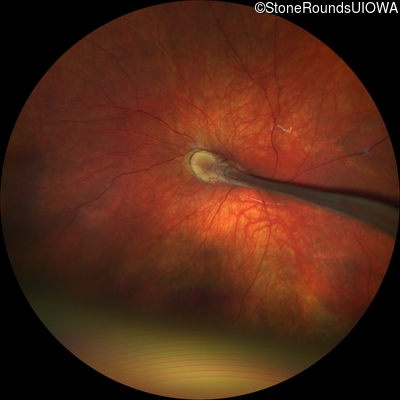

AD Familial Exudative Vitreoretinopathy (IIIE2b)

Age at visit: 23 months

This 23 month old male has had nystagmus since shortly after birth. He was born at term (7lbs 12oz).

AD Familial Exudative Vitreoretinopathy FZD4 Ser228Arg AGC>CGC   AD